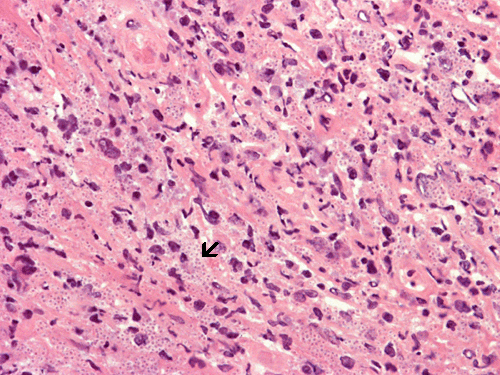

Histoplasmosis, HE stain: Note the numerous small gray dots (arrow). Histoplasma is one of the very few fungal organisms that can be easily visualized on slide without special stains.